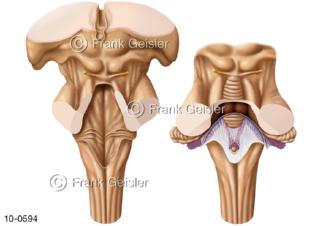

Bildergalerie Nervensystem

Bilder zum Nervensystem,dem Gehirn, Teil des zentralen Nervensystem, Zentralnervensystem ZNSmit Rückenmark, Abbildungen zum Nervengeflecht (Nervenplexus), die Verflechtungen von Nervenfasern, aus der Wirbelsäule hervortretende Nervenäst sowie Nervenzellen der Nerven